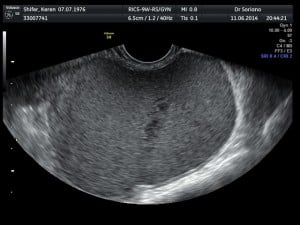

אפשרויות אבחון

אבחון אנדומטריוזיס מתבצע במספר שלבים: יש להתחיל בהכרת כלל התסמינים של המטופלת, מתי החלו, מה עוצמתם, מיקומם, מידת ההשפעה על איכות חייה, והאם ישנן קרובות משפחה הסובלות מכאבים דומים או אובחנו כסובלות מאנדומטריוזיס. אבחון זה המבוסס על הכרת התסמינים הינו חשוב ויש לבצעו ביסודיות. ניתן להעזר בשאלון מובנה כגון שאלון זה : האם את סובלת מאנדומטריווזיס?.  בהמשך מבצעים בדיקה גופנית,  באם ניתן בדיקה גינקולוגית, להערכת כאב ורגישות באזורי האגן. לבדיקה הגינקולוגית ישנה חשיבות רבה למישוש מעורבות רקטווגינלית ומידת מעורבות האגן. לעיתים ניתן להימנע מבדיקה גינקולוגית ולהשלים את המידע עי בדיקת אולטראסאונד . בהמשך יש לבצע בדיקת אולטראסאונד ייעודית לאנדומטריוזיס  אשר מאפשרת זיהוי של מעורבות שחלתית , מעורבות עמוקה של מוקדי אנדומטריוזיס והערכת חומרת המחלה. בדיקה זו מבוצעת במרפאתנו ע"י דר׳ אלדר וולפרט מומחה בתחום האולטראסאונד הגינקולוגי. במקרים חשד למעורבות עמוקה של שלפוחית השתן עו המעי ניתן להיעזר בבדיקות נוספות כגון ציסטוסקופיה בדיקת MRI או קוןלונוסקופיה על מנת להגדיר היטב את מידת חומרת הממצאים.

הטיפול הלפרוסקופי באנדומטריומה ציסטה בשחלה

הטיפול באנדומטריומה דורש תשומת לב מיוחדת.  אנדומטריומה היא ציסטה שחלתית הנגרמת כתוצאה מהצטברות דם כתוצאה מפעילות רקמת אנדומטריוזיס בשחלות. ציסטות אלו מכילות דם ישן שהצטבר לאורך זמן, ולכן מכונות לעיתים "ציסטות שוקולדיות" בשל צבע הנוזל הכהה שבתוכן. נוכחות של אנדומטריומה עשויה להופיע כממצא מקרי במהלך בדיקת אולטרסאונד או כבעת בירור של כאבים עזים במהלך הווסת או כאבים כרוניים באגן. במקרים רבים האבחון נעשה בעת בירור אי פוריות.  אנדומטריומה יכולה להיות חד או דו צדדית, בגדלים שונים מ 1-20 ס״מ בד״כ מתגלית בגדלים של 3-5 ס״מ. אנדומטריומה לעיתים רחוקות הינה ממצא בודד ובמקרים רבים מעידה על נוכחות מוקדים נוספים ולכן בכל חשד לאנדומטריומה יש לבצע אולטראסאונד ייעודי לאנדומטריוזיס לשם בירור מקיף על היקף המחלה. נוכחות של ציסטות שחלתיות אנדומטריומות מעיד במקרים רבים על חומרת המחלה ומחייבת לעיתים התערבות כירורגית. במהלך הערכה יש להכיר את כלל התסמינים, את חומרת הממצאים, את הרזרבה השחלתית והאם קיימת בעיית פוריות האם בוצעו ניתוחים קודמים, האם מדובר בציסטה חד או דו צדדית והאם קיימים ממצאים נוספים ודרגת חומרתם.